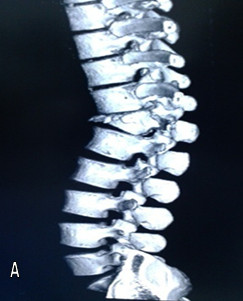

Volver a los detalles del artículo Espondilodiscitis tuberculosa. Presentación de un caso